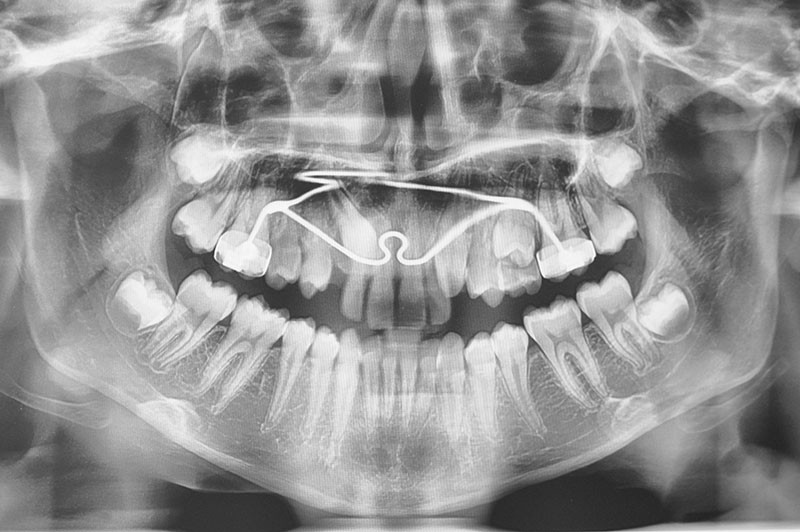

chirurgie à visée orthodontique : extractions de dents de sagesse, dégagement de dents incluses, poses de mini-vis et mini-plaques…